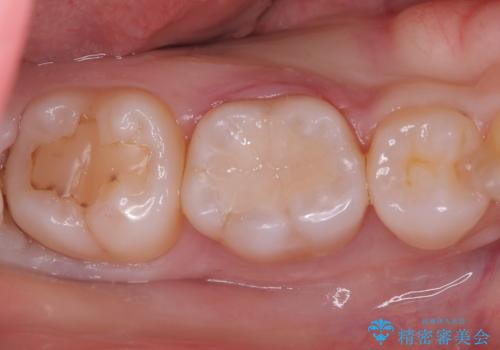

侵襲性歯周炎。前歯の歯周補綴

- 前歯がグラグラすることを主訴に来院されました。

再生治療後、歯周補綴を行っております。

歯周病が進行してしまった歯に対し、再生治療および歯周補綴を行うことで歯周組織の安定を得ることができました。